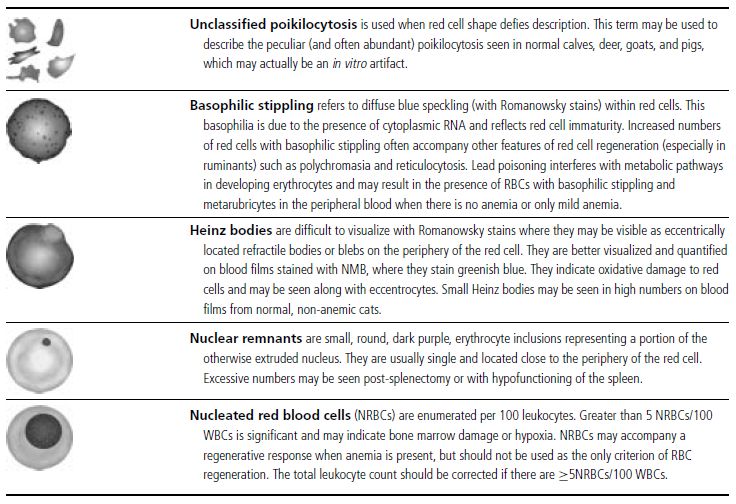

In the common domestic animals, mature erythrocytes are biconcave disks that are highly deformable, allowing them to travel through small capillaries and deliver oxygen to tissues (see Table 1.1). Erythrocyte aging and certain pathological conditions can cause RBCs to assume unusual shapes, which may result in increased rigidity. Rigid RBCs are susceptible to mechanical injury and are less effective in delivering oxygen. Exposure to stagnant environments (pooling of blood in a cavernous, hypoxic space), certain serum biochemical abnormalities, antibody-mediated membrane injury, and mechanical injury can alter the normal biconcave shape. Sometimes, RBC morphologic changes are associated with specific diseases or conditions, but the mechanism of the shape change is not clear (see Table 1.1 for diagrams of various types of RBC morphology).

See Figs 1.3–1.24 for pictures of various types of RBC morphology.

Table 1.1 Erythrocyte morphology